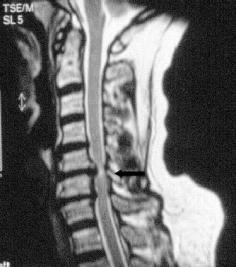

Same applies for abnormalities in the bladder function or walking disorders. Due to pressure on the spinal cord permanent damage could appear. This clinical picture is called Myelopathy.

Based on the examinations and the anamnesis important indications for the causes of the pain come clear. This will be one of the most important indications for an operative or conservative therapy. In addition to that, conventional X-ray as well as a magnetic resonance tomography (MRI) could be helpful.

Anatomical changes in the structure of bones will be determined by a computed tomography. If there is a suspicion of a disease of the spinal cord or a dysfunction of the function of the nerves, an electrophysiological examination will be organized. Similar to an electric lead the electrophysiological examination tries to measure the permeability of the nerve tracts.